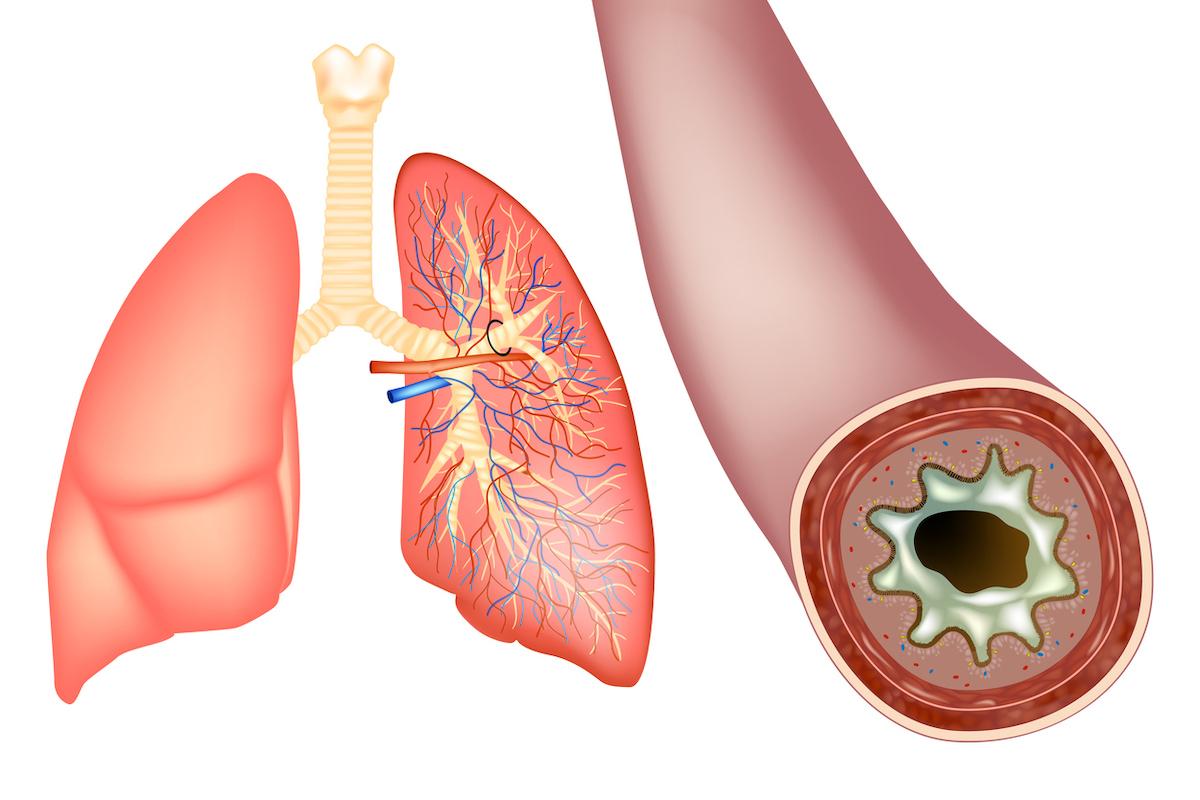

Caillot sanguin

- utah778/IStock

Chaque année, on estime qu’entre 65 et 130.000 personnes sont touchées par une embolie pulmonaire en France. Cause fréquente d’hospitalisation, cette affection se caractérise par l’obstruction d’une artère pulmonaire ou de l’une de ses branches par un caillot de sang. "Elle provoque des dommages au niveau du poumon atteint et la partie lésée ne peut plus fournir d’oxygène à l’organisme", note Ameli Santé, la plateforme de l’Assurance maladie.

Dans la majorité des cas, l’embolie pulmonaire est la conséquence d’une phlébite profonde, qui intervient généralement au niveau des jambes. Également appelée thrombose veineuse, la phlébite est due à la formation d’un ou de plusieurs caillots dans une veine profonde pouvant se déplacer dans la circulation sanguine et se loger dans les poumons, ce qui conduit à une embolie pulmonaire.